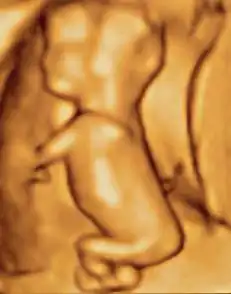

Weeks 17 to 25 (3.6 to 6.6 months)

A woman pregnant for the first time (nulliparous) typically feels fetal movements at about 21 weeks, whereas a woman who has given birth before will typically feel movements by 20 weeks.[17] By the end of the fifth month, the fetus is about 20 cm (8 in) long.